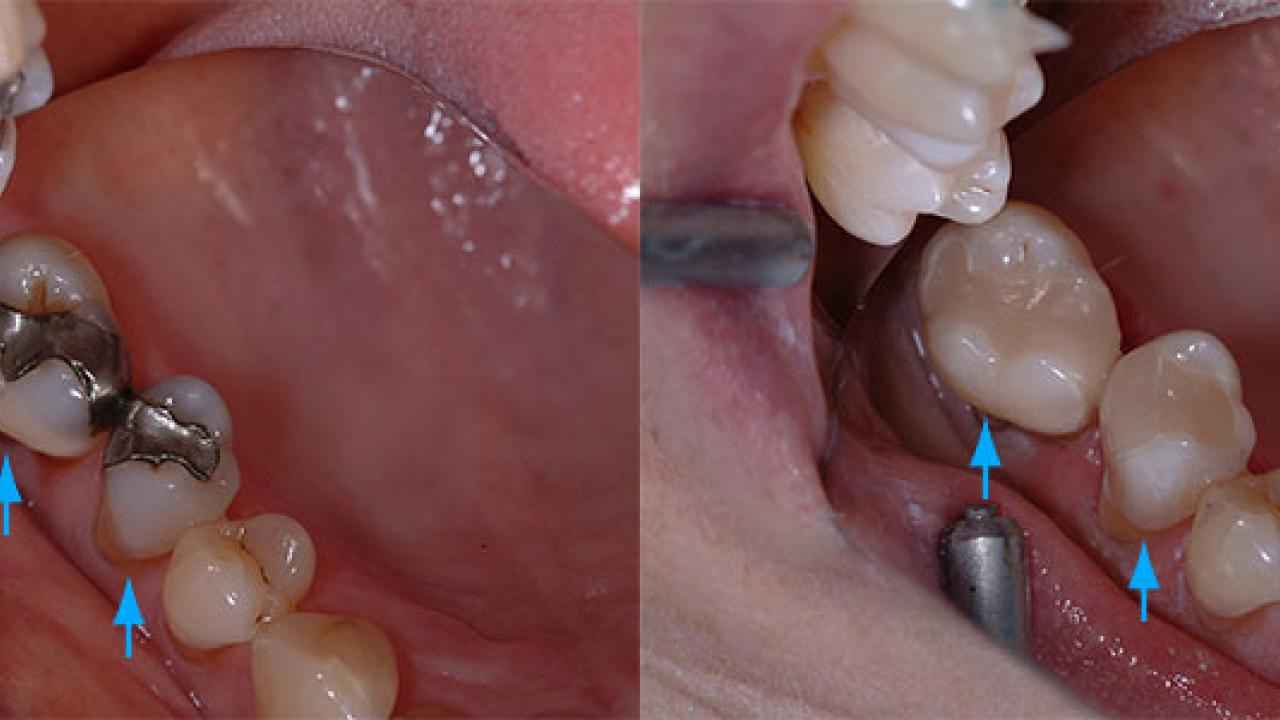

We’d like to let our results do the talking. Check out some of our amazing transformations in our Smile Gallery, combining a mixture of tooth coloured restorations, implant treatments, crowns, veneers, tooth whitening and full mouth rehabilitation.